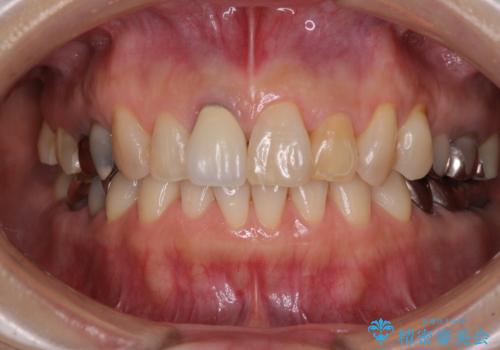

前歯は神経を取り除いて変色した歯や金属の縁が見える歯などがあり審美的に気になっていましたが、治療するかどうかは悩んでいらっしゃいました。

ところが、奥歯の治療を開始する前に、神経が失活して根尖部に病変のある前歯が著しく痛み出したため、根管治療を行うこととなりました。

奥歯の治療をしている間に前歯の治療をどのように勧めるのか検討していただき、最終的には4歯を一度に治療し、審美的に仕上げることとしました。